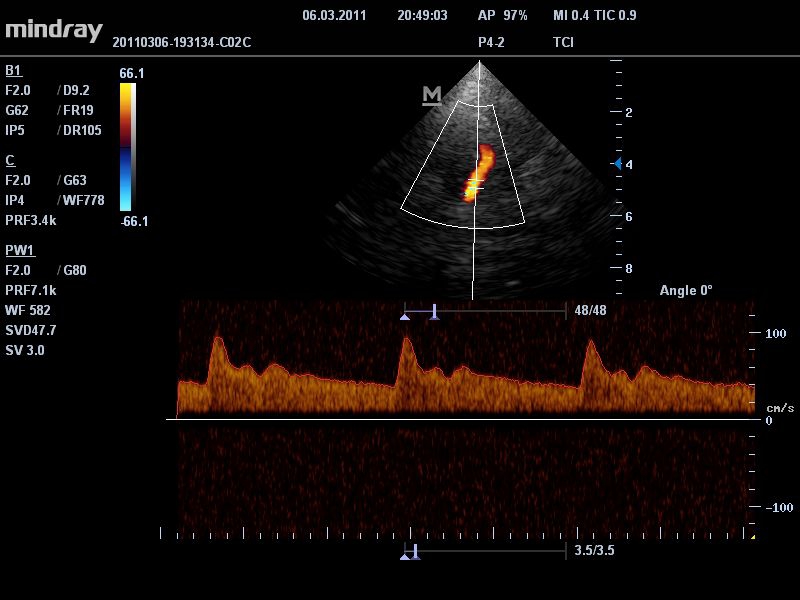

Mindray DC-T6

Ультразвуковая система Mindray DC-T6 – это инновационный аппарат для проведения высокого уровня диагностики с качественной визуализацией и широким спектром применения. Платформа рекомендована для использования в коммерчески многопрофильных медицинских учреждениях и государственных лечебных клиниках.

Импульсно-волновой допплер:

Да

• Режимы сканирования: B/M/CFM/PDI/Направленный PDI/PW, HPRF, Тканевая гармоника, М- и цветной М-режим.